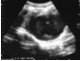

79.患者,女,16岁。周期性下腹疼痛伴排尿困难,月经未来潮。超声检查见图,最可能的诊断是()